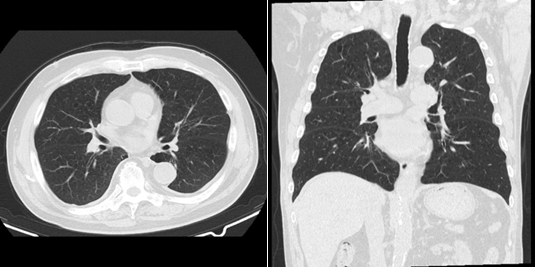

肺低線量CT

レントゲン同等の低線量で肺内チェックできます。男性死亡率第1位、女性第2位の肺がんはレントゲンだけでは見落としを逃れることができません。50歳以上の方や喫煙歴の長い方、粉塵業務に従事されている方、家族歴のある方によりお勧めします。肺がん以外にも、結核や肺炎、肺気腫、気胸、胸部大動脈瘤などの病気を見つけることに優れています。